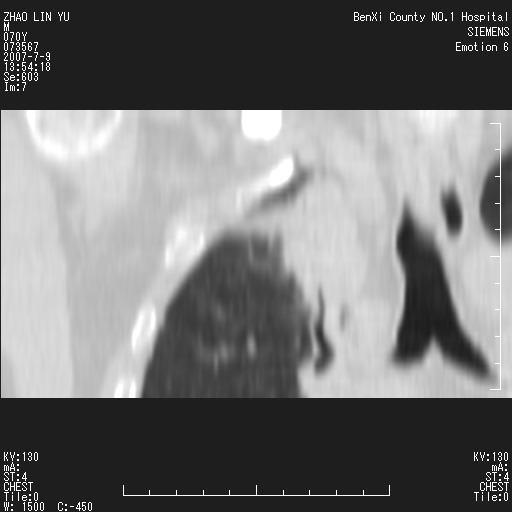

以下是引用王靖旗在2007-7-10 17:12:00的发言:[br] 男、70、咳嗽两个月,半年前换瓣手术,胸片未见异常,于昨天行x片发现右肺上野大片影,行ct扫描,这里是减薄图像,余肺正常。明天晚上会有增强扫描片,到时我会上传。[br][br] 冠状位请大家细看,应该是有意义的,[br][br] 请大家先看平扫发表意见。[br][br]

[br]冠状面[br]

以下是引用zhangzhongshou在2007-7-10 21:43:00的发言:[br]右肺上叶周围型肺癌,以孤立型细支气管肺泡癌可能性大。